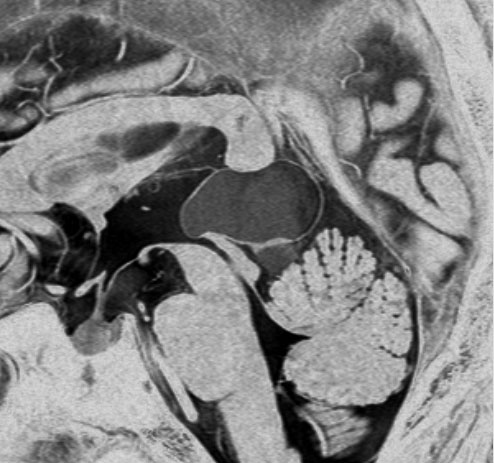

松果体細胞腫の例4(のう胞性腫瘍)

30代女性ののう胞性の松果体細胞腫です。これは大きな松果体嚢胞とほとんど画像では区別がつかないものでした。でも腫瘍ののう胞壁(液体の入っている袋の壁)の後方がガドリニウム増強されていてごく一部が実質性であることが解ります。